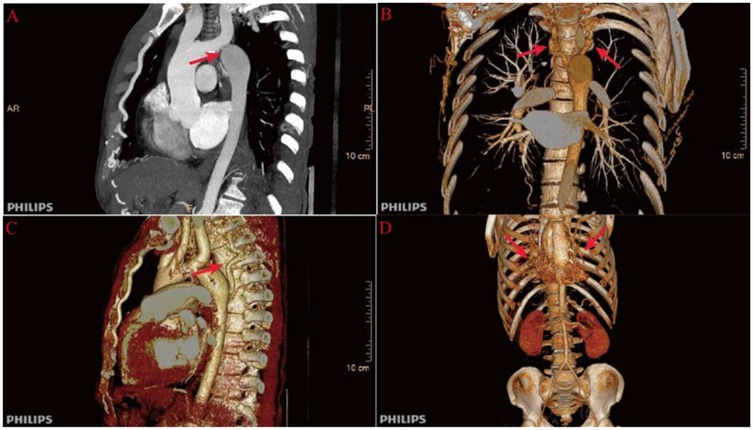

Upon admission to our institution, significant interlimb blood pressure discrepancies were noted: 163/91 mmHg (right upper limb), 159/88 mmHg (left upper limb), 110/82 mmHg (right lower limb), and 102/69 mmHg (left lower limb). On physical examination, cardiac auscultation did not reveal any characteristic murmur suggestive of aortic coarctation (CoA). Cranial CT confirmed a hemorrhagic lesion involving the left basal ganglia, thalamus, and posterior lateral ventricle (approximately 9 ml), alongside multiple chronic infarcts, leukoencephalopathy, and cerebral atrophy. Chest CT revealed multiple bronchiectases with infection in the left lung with concurrent infection, as well as a severe “sandglass-shaped” narrowing at the aortic isthmus, with a minimum lumen diameter of 5 mm and calcification of the descending aortic wall. The aortic sinus was aneurysmally dilated to approximately 46 mm.

Further evaluation using computed tomography angiography (CTA) confirmed severe CoA, with near-complete interruption of the descending aorta at the isthmus and extensive collateral circulation, including prominently dilated and tortuous internal thoracic arteries (Figure 1). The renal arteries were assessed and found to be unremarkable, with preserved renal function throughout hospitalization.

Figure 1

Preoperative computed tomography angiography (CTA) findings. (A) Severe narrowing at the aortic isthmus (“sandglass-shaped” coarctation, arrow); (B, C) Markedly dilated and tortuous paravertebral arteries, demonstrating extensive collateral circulation; (D) Prominent internal thoracic arteries serving as major collateral pathways.

Figure 5

Scattered calcified plaques are observed in the walls of the aortic arch and brachiocephalic trunk, with irregular lumens as shown in (A). The descending aorta shows poststenotic aneurysmal dilation, with dimensional measurements provided in (B).